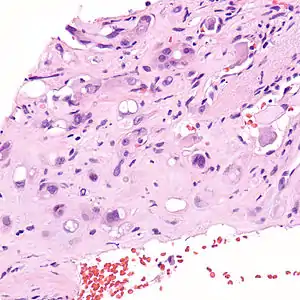

Hemangioendotelioma epitelioide

Hemangioendotelioma epitelióide (HEE) é um raro tumor vascular, inicialmente descrito por Sharon Weiss e Franz Enzinger, o qual tanto clinicamente quanto histologicamente é intermediário entre o angiosarcoma e o hemangioma. No entanto, alteração genética distinta, diagnóstica da patologia, foi recentemente descrita para HEE, indicando que ele é realmente uma entidade separada tanto do angiosarcoma quanto do hemangioma.

O hemangioendotelioma epitelióide é um sarcoma de partes moles e é geralmente considerado um câncer vascular, na medida em que as células "lesionais" expressam marcadores de superfície típicos de células endoteliais (células que revestem o interior dos vasos sanguíneos). Originalmente, foi descrito como ocorrendo mais comumente nas veias das extremidades (braços e pernas) e em dois órgãos, o fígado[1] e os pulmões. Desde então tem sido descrito em órgãos por todo o corpo. Além do fígado e dos pulmões, os ossos e a pele foram os órgãos mais freqüentes.